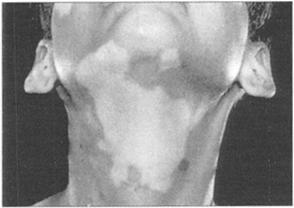

这部分包括常见皮肤病的临床图片:白癜风(图240);特应性湿疹(图241);肘部银屑病(图242);足底银屑病(图243);痤疮(图244);高胆固醇血症导致的黄色瘤(图245);系统性红斑狼疮的蝶形红斑(图246);血管炎时的皮疹(图247)。

图240 白癜风解剖